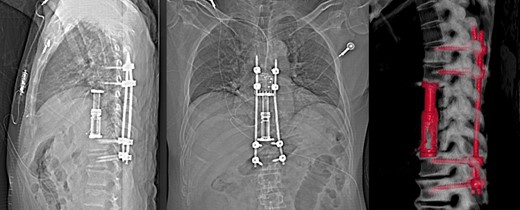

At time of manuscript patient is 10 month post-surgery, he remains on antibiotic therapy (15 months of continuous treatment) with low dose tigecycline, bedaquiline, clofazimine and cefoxitin, which are well tolerated. Imaging of the spine at 3 months postoperatively shows early signs of bony fusion, preservation of alignment with no hardware complications (Fig. 4), without progression of infection. Patient remains free of neurological deficit and is ambulating normally without back pain.

X-ray and 3D reconstruction following non contrast CT thoracic spine, showing final hardware position and spinal alignment after T8–T10 vertebrectomy, reconstruction with expandable cage and percutaneous pedicle screw fixation of T6–T12 (Nuvasive, San Diego, CA).